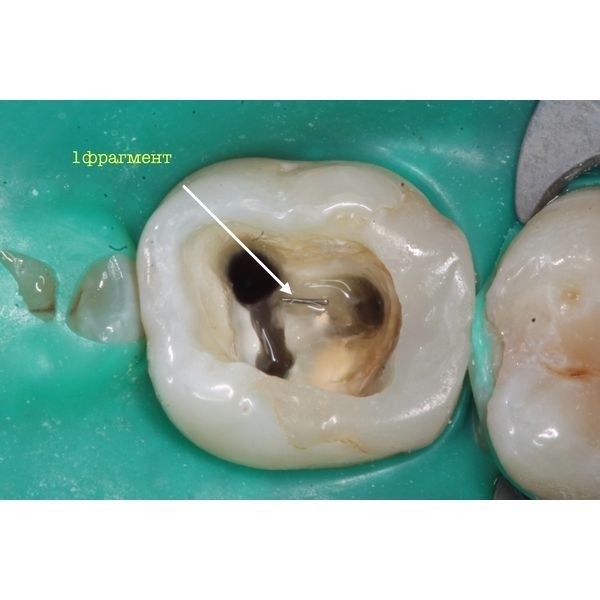

При осмотре под микроскопом можно было увидеть 2 фрагмента инструментов.

Лечение проходило в 2 этапа. На первом приёме удалось извлечь один фрагмент, после чего 3 корневых канала обработали и заполнили (обтурировали) кальцийсодержащим препаратом.

Уже после первой процедуры все симптомы прошли. Следующее посещение назначили через 2 недели, 16 ноября. Пациенту извлекли второй фрагмент и запломбировали каналы с использованием гуттаперчи.